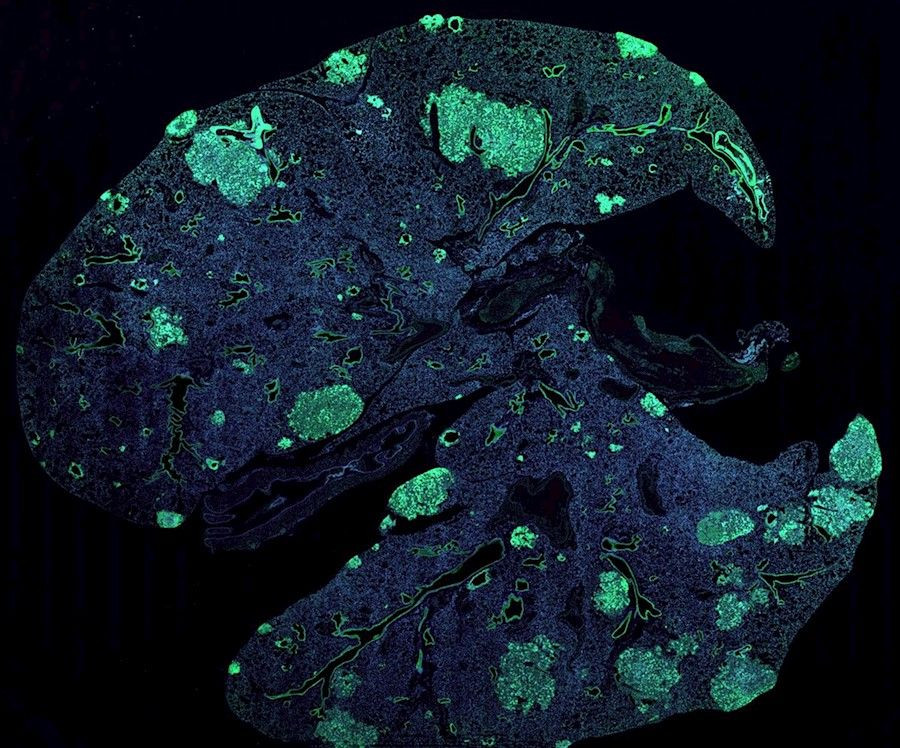

Para eliminar MaTAR 25, los investigadores diseñaron una pequeña pieza de ácido nucleico que reconoce y se une a su secuencia. Una vez unida, esa molécula, conocida como oligonucleótido antisentido, alerta a una enzima dentro de las células para que destruya el lncRNA. Cuando los investigadores inyectaron esta molécula en el torrente sanguíneo de ratones, alcanzó las células tumorales y degradó la mayor parte del MaTAR 25, con efectos dramáticos.

"Cuando hicimos la histología de los tumores descubrimos que eran muy necróticos, lo que significa que hubo mucha muerte celular después de que este ARN se degradara --recuerda Spector--. Y obviamente, ese es un hallazgo importante, pero igualmente, si no más importante, encontramos un reducción muy significativa de la metástasis a los pulmones. Así que esto realmente nos dio datos muy interesantes de que esta molécula de ARN tiene cierto potencial como objetivo terapéutico".